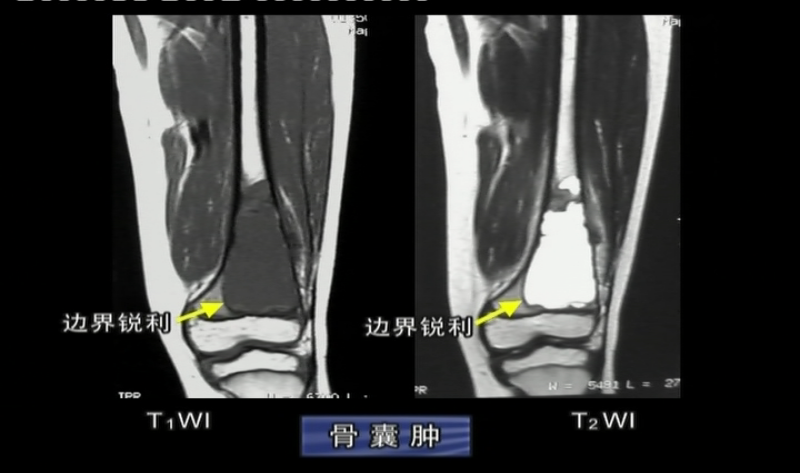

骨囊肿:发病于青少年,男性多见 ,良性

影像表现:1、多发生于长骨干骺端,肱骨上段多见;2、膨胀性中心性生长;3、边缘有薄层硬化边;4、长轴与骨干平行;5、合并病理性骨折